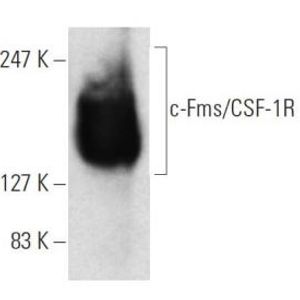

AUG 07, 2023CancerAn exciting new cancer drug has recently entered into a phase 1 clinical trial supported by promising pre-clinical work. ...